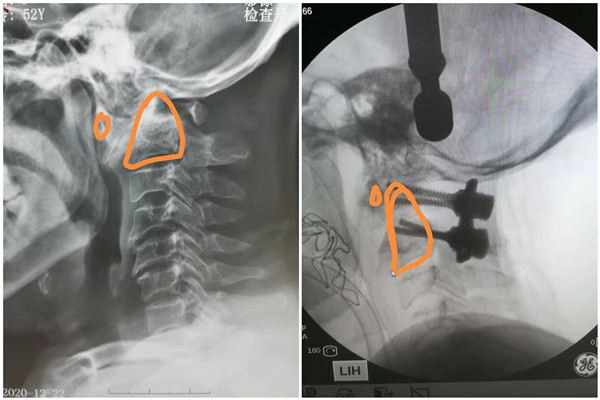

1月4日,2021年第一个工作日,患者进入手术室。手术由李芳教授及严百惠医师麻醉,李浩鹏主任及臧全金教授主刀、郭帅、欧阳彭荣博士作为助手,手术室彭维护士辅助,黄亚娟、孙丽君行诱发电位监护下完成。麻醉过程中,臧全金教授组熟练地进行手术床牵引头架更换及牵引准备。麻醉完成后即进行颅骨牵引,翻身俯卧位,通过大重量颅骨牵引发现寰枢椎部分复位。手术采用后入路,术中臧教授细致操作,寰椎后弓、枢椎椎弓根、静脉丛、枕大神经逐一清晰地显露出来,连平时难以见到的寰枢椎侧块都清晰的置于术野后,接是精准的寰枢椎螺钉置钉,通过后路松解发现寰枢椎仍未完全复位。翻身更换为仰卧位,经口咽行前路松解,经显露,影像片上寰枢椎的增生及脱位状态跃然眼下,通过前路的骨性及软组织松解,寰枢椎之间活动度增大。再次翻身,通过内固定装置的调整圆满的完成了寰枢椎的复位。除去手术翻身及消毒准备的时间,手术共花费约5小时,出血约200ml。术后患者清醒后即感觉肢体肌力较术前好转。